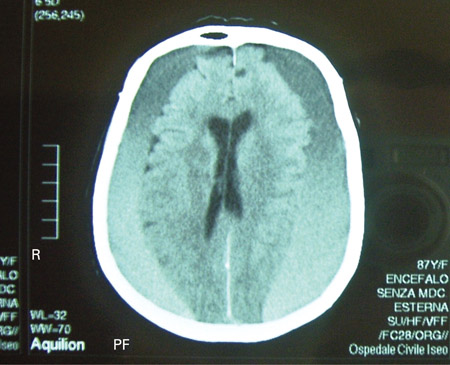

Subdural haematoma

CT scan of the brain of an 80-year-old man with a gait disorder and a progressive cognitive impairment dating back about 6 months, showing a bilateral chronic subdural haematoma up to the convexity

Adapted from BMJ Case Rep. 2009;2009:bcr06.2008.0130